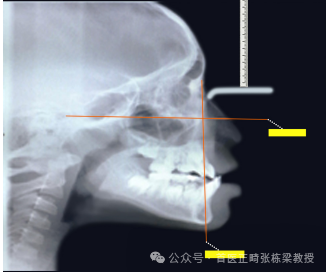

我们会给孩子拍X光片,设定FH平面,找出眶点、耳点、鼻根点,从鼻根点向下做垂线,分析上颌骨的A点和下颌骨的颏前点距离,这条线的距离,是我判断地包天骨骼问题,比较常用的方法。

但是如果是骨性地包天的问题,那我们就需要使用RME+前方牵引,促进上颌骨往外拽。

那么我们在10岁以前通过加以外力,可以使得上颌骨往下往前生长,这时候骨缝就会撕裂开,那纤维组织就会形成新骨叫牵张成骨,这是一个促进上颌骨发育的方法。

那么前方牵引的反作用力,同时也可以控制下颌骨过度的生长,因此前方牵引是做反颌一个有效的方法。